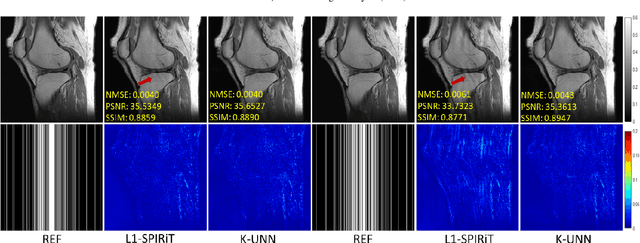

Abstract:Recently, untrained neural networks (UNNs) have shown satisfactory performances for MR image reconstruction on random sampling trajectories without using additional full-sampled training data. However, the existing UNN-based approach does not fully use the MR image physical priors, resulting in poor performance in some common scenarios (e.g., partial Fourier, regular sampling, etc.) and the lack of theoretical guarantees for reconstruction accuracy. To bridge this gap, we propose a safeguarded k-space interpolation method for MRI using a specially designed UNN with a tripled architecture driven by three physical priors of the MR images (or k-space data), including sparsity, coil sensitivity smoothness, and phase smoothness. We also prove that the proposed method guarantees tight bounds for interpolated k-space data accuracy. Finally, ablation experiments show that the proposed method can more accurately characterize the physical priors of MR images than existing traditional methods. Additionally, under a series of commonly used sampling trajectories, experiments also show that the proposed method consistently outperforms traditional parallel imaging methods and existing UNNs, and even outperforms the state-of-the-art supervised-trained k-space deep learning methods in some cases.